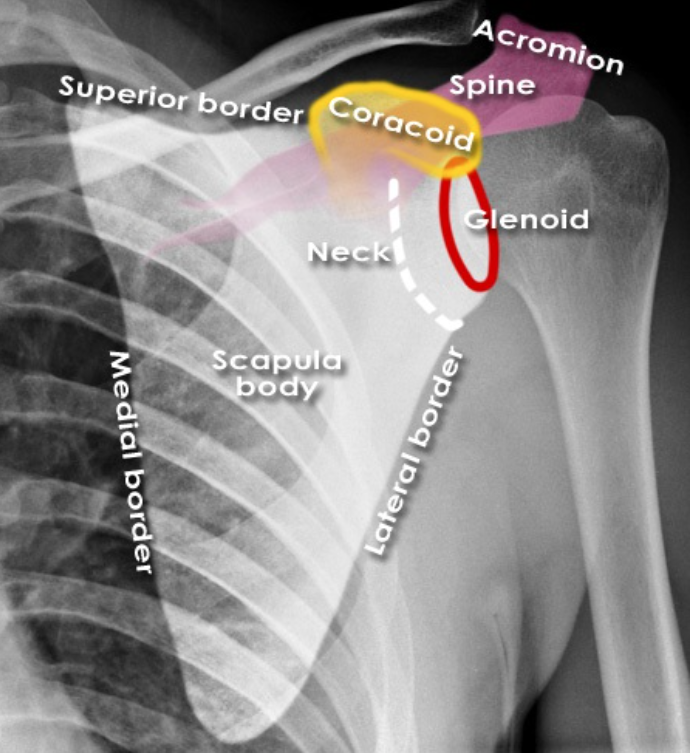

Label the following diagram

1. Spine of scapula

2. Clavicle

3. Acromioin

4. Humerus head

5. GH joint

6. Shaft of humerus

7. Medial boarder of scapula

8. Humeral head (greater tuberosity)

9. acromion

10. GH joint

11. Lateral boarder of scapula

12. clavicle

13. coracoid process